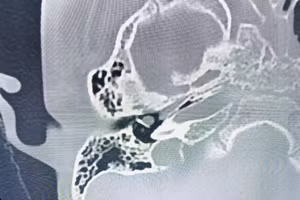

16/06/2023 09:18 GD&TĐ - Các bác sĩ Bệnh viện Đa khoa tỉnh Quảng Ninh vừa phẫu thuật nội soi điều trị u tai giữa bẩm sinh (Cholesteatoma) cho một bệnh nhi 5 tuổi.

17/05/2023 20:53 GD&TĐ - Ngày 17/5, Bệnh viện Trung ương Quân đội 108 cho biết đã phát hiện một trường hợp mắc viêm tai chũm. Đây là căn bệnh hiếm gặp, nguy hiểm.